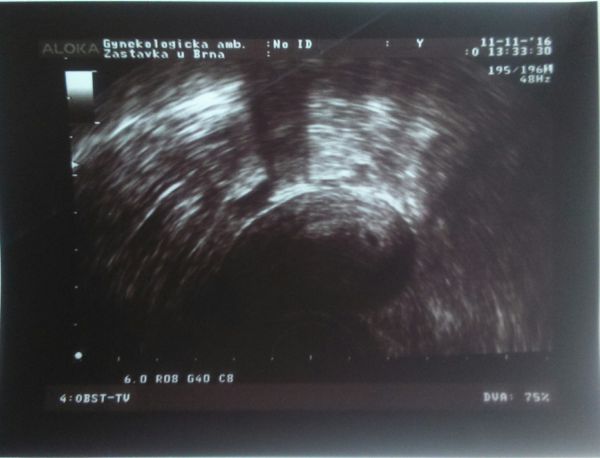

Tak dneska jsem byla v CARu. hCG 7365 a odpovídáme 4+5. Za čtrnáct dní znovu na ultrazvuk, kde už by mělo být vidět srdíčko :-) mám hroznou radost.... :€O: